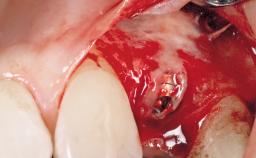

After the placement of three diameter-reduced two-piece implants the bone is augmented with autologous bone chips and DBBM particles to enlarge the crest volume. The surgery is completed with the application of two membrane layers and primary wound closure.